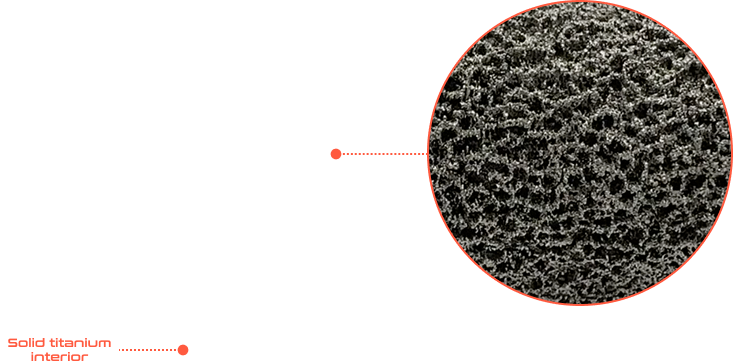

Additive manufacturing or 3D printing via electron beam melting enables rapid response.

Advanced osseointegration is designed into every implant. Our manufacturing process allows geometry and surface texture to be tuned to encourage bone growth for maximum fixation. We are osseointegration specialists.